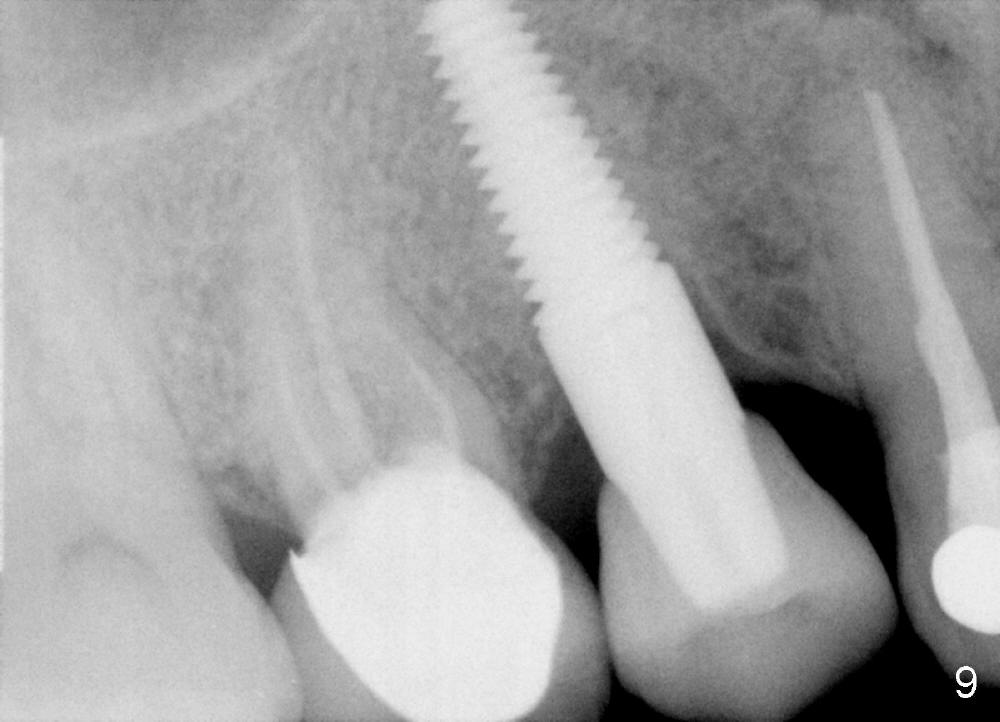

Fig.9 is taken 19 months post cementation of the implant crown. There is no bone resorption around the implant.